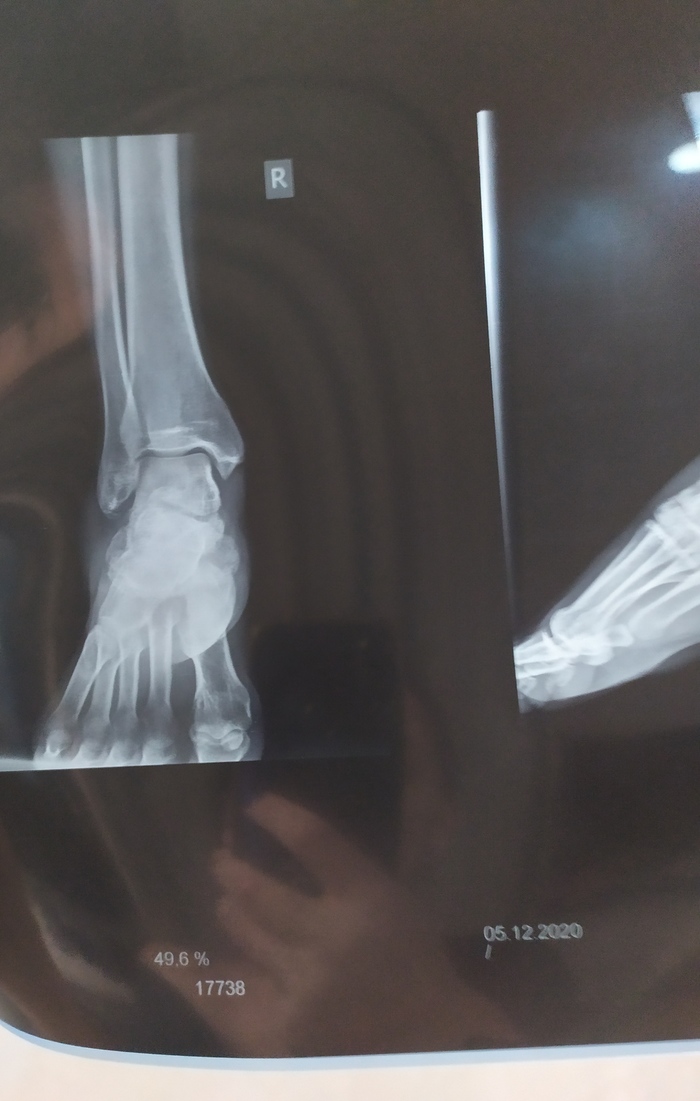

Итоговый вариант с внутренними мягкими "стаканами" в ногах, которые в точности повторяют форму мышц.